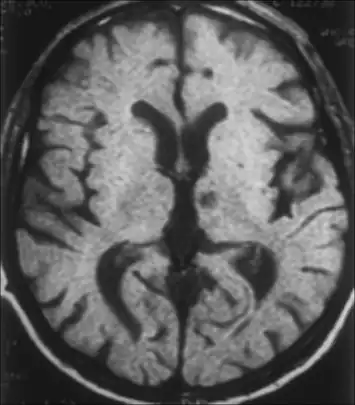

Left subthalamic nucleus stroke caused contralateral hemiballism.

Left subthalamic nucleus stroke caused contralateral hemiballism.- Hyperglycemia-induced involuntary movements (in this case, not hemiballismus, but hemichorea (chorea of one side of the body) and bilateral dystonia) in a 62-year-old Japanese woman with type 1 diabetes.